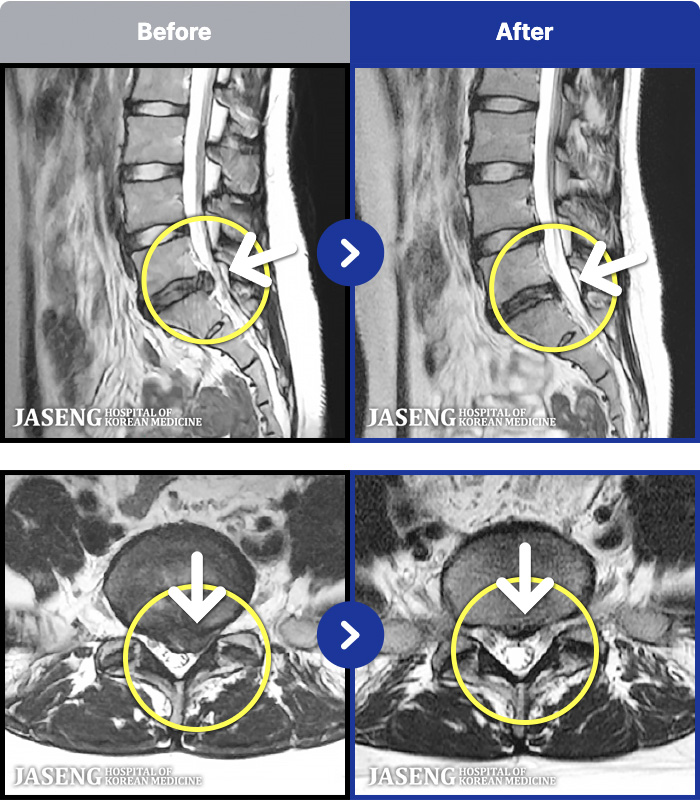

1,240 MRI ũ ʸ Ȯϼ.

MRI ġ

㸮 ϻ .